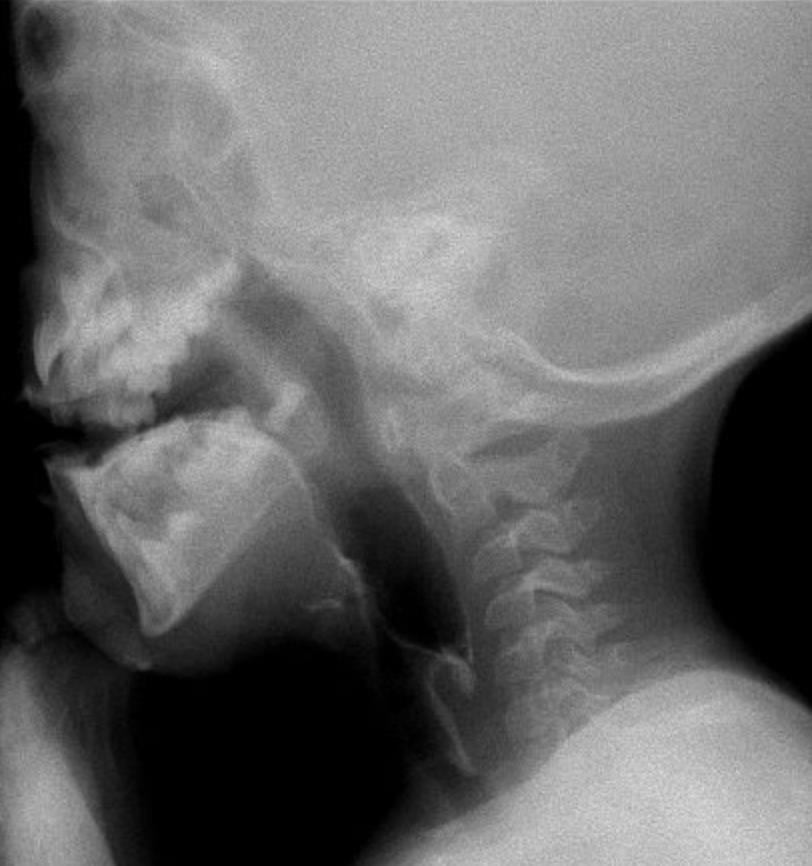

Videofluoroscopy

ORAL PREPARATORY PHASE IN EATING SOLID FOOD

✓ Loss of food out mouth, pushed out with tounge

✓ Food in anterior sulcus

✓ Limited tongue movement

✓ Problem about turning the food into bolus formation

✓ Food in valleculae and pharynx,

pre swallow

✓ Jaw grading inappropriate

ORAL PREPARATORY PHASE IN DRINKING LIQUID FOOD

✓ Loss of food out mouth

✓ Liquid in anterior sulcus

✓ Food pushed out with tounge

✓ Food in valleculae and pharynx, pre swallow

ORAL PROPULSIVE. PHASE:

✓ Food or liquid remains in anterior and/or lateral sulcus

✓ Food or liquid remains on floor of mouth

✓ Limited posterior tongue movement

✓ Reduced base of tongue action

✓ Tongue-soft palate contact incomplete

✓ Multiple swallows per bolus

✓ Delayed oral transit time

PHARYNGEAL PHASE

✓ Nasopharyngeal regurgitation

✓ Slow bolus passage through Pharynx

✓ Reduced pharyngeal contraction/motility

✓ Residue cleared with next swallow

✓ Residue not cleared

✓ Reduced hyolaryngeal execursion

✓ Penetration to underside of epiglottis

✓ Penetration to laryngeal vestibule

✓ Aspiration before, during and after swallow

✓ Aspiration respons: not effective cough, no cough – silent aspiration

ESOPHAGEAL PHASE

✓ Slow bolus passage through UES

✓ Residual on UES

✓ Cricopharyngeal dysfunction

✓ Slow bolus passage through esophagus